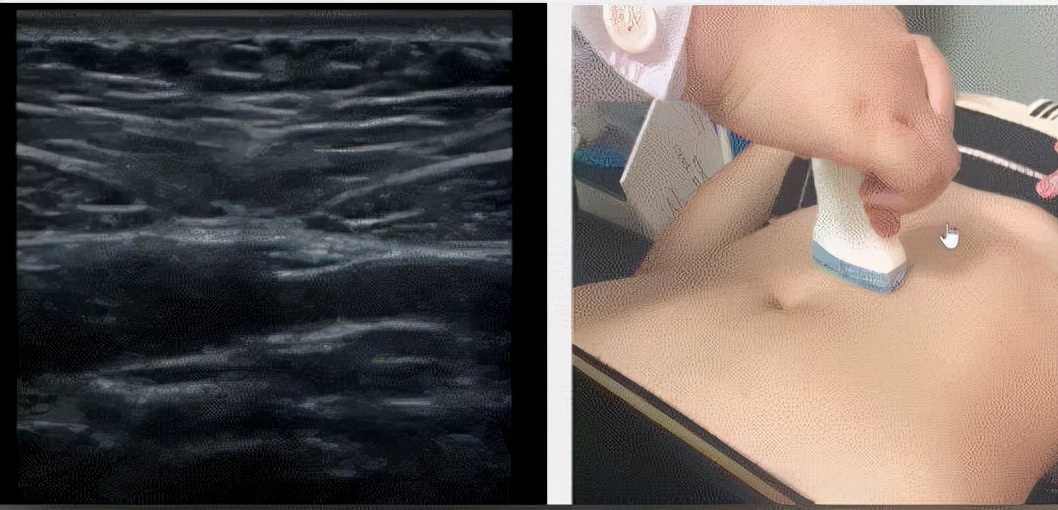

腹直肌超声检查是诊断腹直肌分离的首选金指标,不仅能有效评估腹直肌分离的程度,还能检测出腹直肌修复的激活程度

超声在进行腹直肌间距测量时,只需提供具体的测量数据会更客观。

5、腹直肌分离的超声检查方法

产妇平躺,将5-7M高频探头放置于产妇腹腔不同位置,观察到两侧腹直肌形态,厚度、腹直肌鞘的延续性。